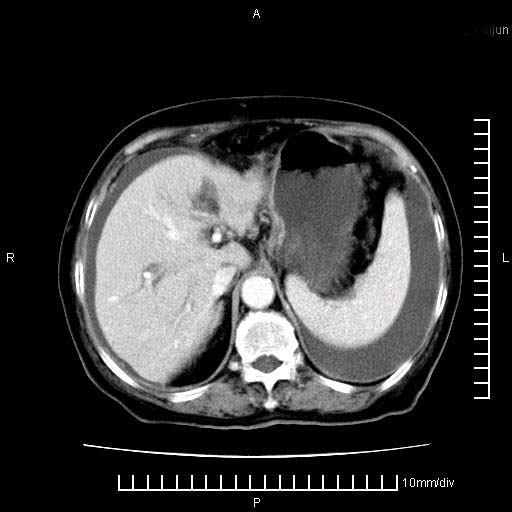

标题: CT28280:腹部增强:女性,80岁

上腹疼痛月余,外院核磁诊断胰腺癌。现临床示右下腹可明显触及包块,可片子上怎么没有看到?

胰腺体部癌累及周围器官,腹膜、粘连

1。胰腺ca伴腹膜腔转移

2。肝左叶低密度灶,考虑转移可能

支持胰腺癌肝内转移,腹水改变。

1、考虑胰腺癌伴腹膜腔转移,胸腹水。

2、肝脏转移可能。

1)考虑胰腺癌并胰腺假性囊肿形成。2)肝内低密度灶,不排除转移。3)右肾盂积水。4)腹水。5)右侧胸腔积液并右肺下叶部分膨胀不全。

考虑胰腺ca伴腹膜腔转移、肝左叶转移、右肾积水。右胸腔积液。